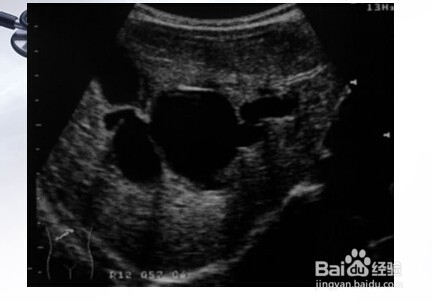

1、一:先天性胆总管囊肿。